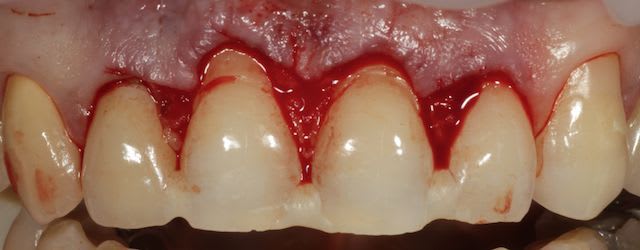

Puisqu'on parle un peu de muco, je vous propose un cas de lambeau positionné coronairement modifié selon la technique dite de Zucchelli.

En fait le principe c'est de reporter la hauteur de tes recessions au niveau des papilles et de faire tes incision en fonctions, effectivememnt le lambeau est dissequé au delà de LMG pour pouvoir suturer sans tension, les papilles saignent parce qu'elles sont été désepithelialisés.

à 6 semaines.